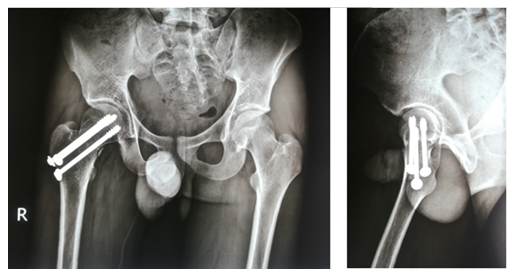

After selecting a case according to inclusion and exclusion criteria, patients were evaluated preoperatively. An elaborate history was taken. This was followed by a general examination and local examination. After admission, patients were put on surface traction to the affected limb with 1/10th of the patient's body weight. All patients underwent preoperative counselling regarding the operative procedure, probable complications, outcome, and other treatment options, along with their merits and demerits. After being informed, written consent was obtained. After preparing the patients for operation, Closed reduction is performed with the patient in the supine position on a fracture table (Figure 1). Reduction was confirmed by C-arm. After reduction, three guide wires are placed, usually in an inverted triangular fashion (Figure 2).

The screw lengths are measured, and drilling is performed using a 4.5 mm cannulated reamer. The screws are then inserted (for the BDSF technique, a specific sequence of middle, then superior, and lastly inferior screw insertion is to be followed). All three screws are inserted less than 5 mm subchondrally (Figure 3,4). In all cases, a prophylactic antibiotic was given. In the postoperative ward, proper fluid and hemodynamic balance were ensured. Change of posture was done twice an hour. The antibiotic was continued for 3 days. Analgesics were given to ensure a pain-free postoperative period. On the first postoperative day, patients were allowed to sit on the side of the bed. Patients were being educated about breathing exercises, isometric quadriceps exercises, gluteal exercises, and ankle pumping exercises. An immediate postoperative X-ray was done (Figure 5). After checking the dressing, on 4th POD, they were discharged from the hospital if their postoperative period was uneventful. Oral antibiotics were given for 10 days. Advice was given to continue isometric quadriceps exercise. Regarding ambulation, they were advised to do non-weight-bearing (of the affected side) crutch ambulation until directed by the physician. Use of elevated toilet seats onwards is also advised. The next follow-up would be given at the 14th POD. The first follow-up was given at 14th POD to check any signs of infection, pain status, and distal neurovascular status. The stitch was removed on the same day. Advice given about isometric quadriceps exercise, active abduction, extension exercise, and stretching exercise of the hip joint. The next follow-up was the 6th week after the operation. The range of motion was tested. An X-ray was done to check callus formation. Improvements were noted. Partial weight bearing was given at this follow-up. Subsequent follow-up was given at 12 weeks and every 4 weeks until union has been achieved or at least 9 months (Figures 6-10).